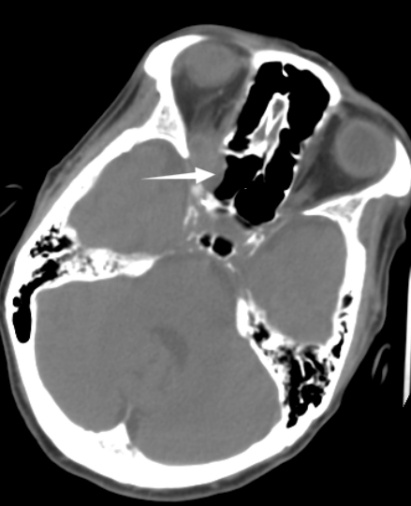

| 右侧视神经孔占位性病变,可见右侧蝶窦外侧骨质缺失,临近眶尖见软组织团块,软组织团块与视神经、眼肌分界不清 图 1 患者入院时头颅CT |

患者,72岁女性,因“头痛伴反应差1 d,呕吐1次”入本院神经外科。患者入院前1 d突发头痛,伴意识状态差,不能行走,伴呕吐1次,呕吐物为胃内容物,无抽搐、发热。入院时体温36.5℃,血压187/97 mmHg(1 mmHg=0.133 kPa),神志嗜睡,表情淡漠,GCS评分12分,双侧瞳孔不等大,左侧直径2.5 mm,直接对光反射灵敏,间接对光反射消失,右侧直径4.0 mm,直接和间接对光反射均消失,双侧巴氏征阴性。既往曾出现右侧眼睑下垂,右眼视力变差,1个月前右眼视力丧失,曾在外院诊断为右侧视神经炎性假瘤,有高血压病史,否认手术史及免疫缺陷病史。入院头颅CT提示右侧视神经孔占位性病灶,视神经脑膜瘤可能(图 1)。头颅MR提示:①右侧基底节区、中脑、脑桥、双侧小脑半球多发斑点状/斑片状新鲜脑梗塞灶;②双侧基底节区、放射冠多发斑点状/斑片状脑梗塞灶或缺血变性灶;③右侧眶尖条片状异常信号灶,性质待定(图 2)。经神经内科会诊后考虑急性脑梗死,转入神经内科治疗,神经内科治疗上给予抗血小板、甘露醇脱水降颅内压、营养神经对症处理。患者入院后反复出现发热,发热原因未明,入院第2天经家属同意后行腰椎穿刺留取脑脊液行高通量基因测序。入院第3天,患者病情加重,神志转昏迷,复查头颅提示:①鞍上池、环池、天幕缘见片状稍高密度,考虑蛛网膜下腔出血。脑干、左侧小脑半球见斑片状低密度灶,范围大致如前,考虑脑梗塞,脑干片状低密度灶密度更低,请结合临床;②脑白质病变,脑萎缩,同前;③右侧眶尖部见片状软组织密度影,大小约16 mm×9 mm,性质待定,同前片,建议MR平扫+增强检查协诊(图 3)。考虑蛛网膜下腔出血合并脑室系统扩张,转神经外科急诊行脑室外引流+全脑血管造影术,脑血管造影未见脑动脉瘤及畸形改变(图 4)。术后转入ICU监护治疗,转入ICU后脱水降颅内压、抗感染、脑保护、预防脑血管痉挛等治疗。患者术后出现双侧瞳孔散大,复查头颅提示蛛网膜下腔出血较前增多,双脑室积血、积气,脑干、左侧小脑半球见斑片状低密度灶。入院第4天,脑脊液高通量基因检测结果报告为烟曲霉感染,脑脊液及血液半乳甘露聚糖检测(GM试验,金域)结果分别为6.19/1.42,阳性。综合病史、CT及MR结果,临床诊断为脑烟曲霉感染,改用伏立康唑注射液积极抗真菌治疗,白蛋白联合激素脱水减轻脑水肿、尼莫地平抗脑血管痉挛及脑保护等综合措施。患者体温热峰下降,但持续深昏迷,神经反应差,入院第7天家属放弃治疗出院。

脑曲霉菌感染合并蛛网膜下腔出血较为少见,文献报道多为个案[8]。本例患者肺部及鼻窦部菌未发现曲霉菌感染临床表现以及影像学表现,但头颅CT可见右侧蝶窦外侧骨质缺失,临近眶尖见软组织团块,软组织团块与视神经、眼肌分界不清。MRI见右侧眶尖见软组织团块,T1WI呈等/高信号,T2WI呈等/高信号,DWI呈等/高信号,ADC呈等/高信号,行脑血管造影时未见眼眶有造影剂聚集,结合患者入院2月前在外院发现右侧视神经孔占位性病变并行激素冲击治疗,因而,临床高度考虑患者右侧视神经孔曲霉菌感染,经激素冲击治疗后此位置的直接蔓延导致颅内曲霉菌感染。遗憾的是,入院后患者病情变化迅速,未能获取右侧视神经孔活检进一步明确诊断。尽管在入院第4天明确脑曲霉菌感染,并给予伏立康唑注射液积极抗真菌治疗,但患者病情进展迅猛未能获得良好预后。本例患者急性多发脑梗死及蛛网膜下腔出血考虑与烟曲霉侵犯嗜血管性有关,颅内组织缺血缺氧性坏死,造成脑血管意外的发生,而曲霉菌引起的变态反应加重或导致了恶性脑水肿,最终造成患者不良预后。